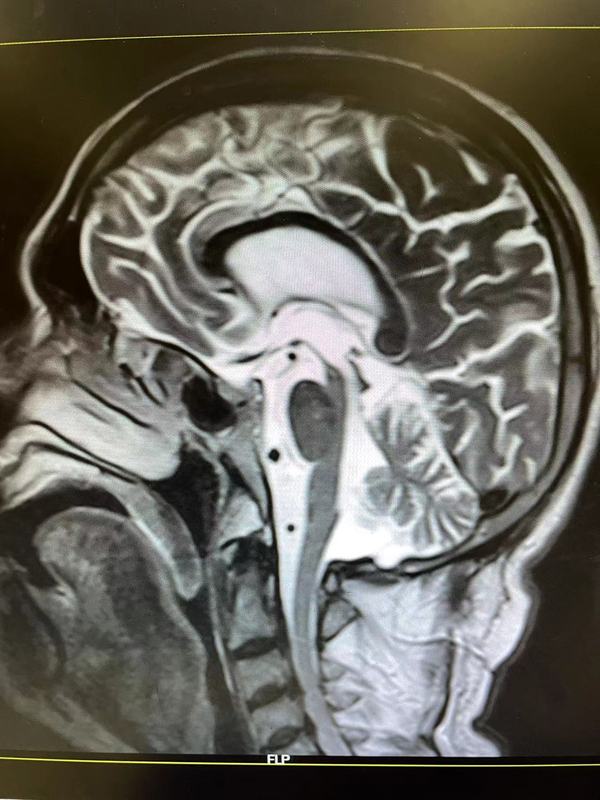

一、概述腦腱黃瘤病(CTX)是一種罕見的常染色體隱性遺傳代謝性疾病,是CYP27A1基因突變造成固醇﹣27羥化酶缺陷致病。固醇-27羥化酶缺乏,膽固醇合成膽汁酸受阻,引起不同組織膽固醇代謝障礙。由于體內(nèi)沉積的膽甾烷醇和膽固醇有神經(jīng)毒性作用,導(dǎo)致中樞-周圍神經(jīng)系統(tǒng)的廣泛損害,出現(xiàn)癡呆、小腦性共濟失調(diào)、延髓麻痹、進行性下肢疼攣性癱瘓和周圍神經(jīng)病,肌腱黃瘤、青少年白內(nèi)障和早發(fā)的動脈硬化。磁共振檢查可見雙側(cè)小腦齒狀核、小腦白質(zhì)T2高信號,可累及小腦腳、腦干錐體束及內(nèi)側(cè)丘系走行區(qū)、腦室周圍白質(zhì)、胼胝體和基底核區(qū),隨病情進展可出現(xiàn)齒狀核T2低信號,可見小腦萎縮。二、臨床表現(xiàn)CTX在不同年齡人的身上,癥狀表現(xiàn)有所不同,嬰幼發(fā)病的患兒以慢性腹瀉癥狀表現(xiàn);幼年型患二常出現(xiàn)白內(nèi)障;少年至青年型患者,則易于多處肌腱出現(xiàn)脂肪堆積的黃瘤;成人型患者可能表現(xiàn)出退行性中樞病變。1.眼睛白內(nèi)障:約75%患者發(fā)生干10歲前,其余25%常發(fā)生于40歲之后。其它表征有眼瞼黃瘤、視神經(jīng)萎縮、眼球突出。發(fā)生視神經(jīng)盤蒼白者占50%,發(fā)生早發(fā)性視網(wǎng)膜衰老合并視網(wǎng)膜血管硬化者為30%。青少年時期發(fā)生雙眼白內(nèi)障者占90%。2.神經(jīng)系統(tǒng)表現(xiàn)中樞神經(jīng)系統(tǒng)在20-30歲間出現(xiàn)錐體系癥狀者占67%,小腦性共濟失調(diào)占60%,智能低下(20歲后)占57%,癲癇(約50%)與周圍神經(jīng)病各占24%。小腦體征以及錐體外系有肌張力障礙、類帕金森癥狀等;神經(jīng)精神病學(xué)癥狀有幻覺、行為改變、躁動、憂郁等。32%表現(xiàn)為智能發(fā)育遲緩,24%出現(xiàn)步態(tài)異常。神經(jīng)系統(tǒng)癥狀中,錐體系小腦性共濟失調(diào)占60%,智能低下占57%,癲癇與周圍神經(jīng)病各占24%。3.周圍神經(jīng)病變感覺異常、肢體末端肌肉萎縮及高弓足等。4.黃瘤介于20-30歲間。發(fā)生在跟腱、手及手肘伸肌、膝蓋及頸部等處;肌腱黃瘤的發(fā)生率占56%。跟腱腫物邊界清、質(zhì)硬、動度差、輕度壓痛,無搏動感。跟腱MR顯示跟腱顯著增粗,肌腱中有黃色瘤形成。5.心血管早發(fā)的動脈硬化及冠狀動脈疾病。6.胃腸道嬰幼兒慢性腹瀉(最早發(fā)生的癥狀);膽結(jié)石(較少見)。7.提早老化早發(fā)性白內(nèi)障、骨質(zhì)疏松、掉牙、動脈硬化及神經(jīng)損傷性的癡呆等。8.內(nèi)分泌甲狀腺功能低下。9.影像學(xué)表現(xiàn)頭顱MRI典型表現(xiàn)有小腦、側(cè)腦室周圍白質(zhì)、基底節(jié)、腦干對稱性的長T2信號,同時伴有大、小腦萎縮,可見小腦齒狀核軟化及鈣化灶。MRS病灶處乳酸峰及脂質(zhì)峰增高,NAA峰降低。三、化驗檢查1實驗室檢查血漿膽甾烷醇及尿膽汁醇含量異常升高,是診斷CTX的實驗室檢查最有用的指標(biāo)。烷醇含量較正常水平高5~10倍,,血漿膽汁醇含量可較正常水平高500~1000倍。腦脊髓液中膽甾烷醇及載體蛋白β上升;皮膚切片培養(yǎng)細胞、血中及肝中的固醇27-羥化酶活性顯著偏低。2.影像學(xué)檢查顱腦MRI見齒狀核及小腦,大腦白質(zhì)的異堂信號。3.基因檢查CYP27A1基因缺陷率為99%-100%。四、發(fā)病機制本病的可能發(fā)病機制是膽酸合成障礙、膽固醇代謝產(chǎn)物膽甾烷醇異常蓄積。健康人體內(nèi),固醇27-羥化酶催化膽固醇氧化反應(yīng),生成27-羥基膽甾醇,后者再經(jīng)膽固醇-7α-羥化酶(CYP7A1)催化生成膽酸及鵝去氧膽酸(CDCA),是人體生成膽酸的最主要途徑。CTX患者膽固醇27-羥化酶活性不足導(dǎo)致CDCA合成不足,進一步引起膽固醇負反饋調(diào)節(jié)性升高,通過膽固醇-膽酸經(jīng)典代謝途徑,使膽甾烷醇及膽汁醇含量升高,并在多個系統(tǒng)內(nèi)大量堆積而引發(fā)相應(yīng)臨床癥狀。五、遺傳機制本病的致病基因是CYP27A1,該基因位于2號染色體長臂q33-qter。CYP27A1編碼由498個氨基酸組成的固醇27-羥化酶,該基因突變造成固醇27-羥化酶活性大大降低。CYP27A1突變有70余種,其中45%屬錯義突變,20%無義突變,18%剪接突變,4%缺失突變,2%插入突變。超過50%的突變發(fā)生于6號至8號外顯子之間,14%位于2號外顯子,14%位于4號外顯子區(qū)域。:絕大多數(shù)的錯義突變通過影響血紅素結(jié)合位點及腎上腺鐵氧還原蛋白結(jié)合位點,破壞固醇27-羥化酶活性;剪接突變導(dǎo)致mRNA快速變性,使翻譯表達失敗。基因突變類型與臨床表型之間并無相關(guān)性:有相同癥狀患者的CYP27A1突變位置及類型可完全不同,在同一家系不同個體之間,臨床表現(xiàn)也可有很大差異。六、治療本病用補充膽酸治療有效??诜﨏DCA750mg/d可使血漿膽甾烷醇、尿膽汁醇水平恢復(fù)正常,并使患者臨床癥狀明顯改善。